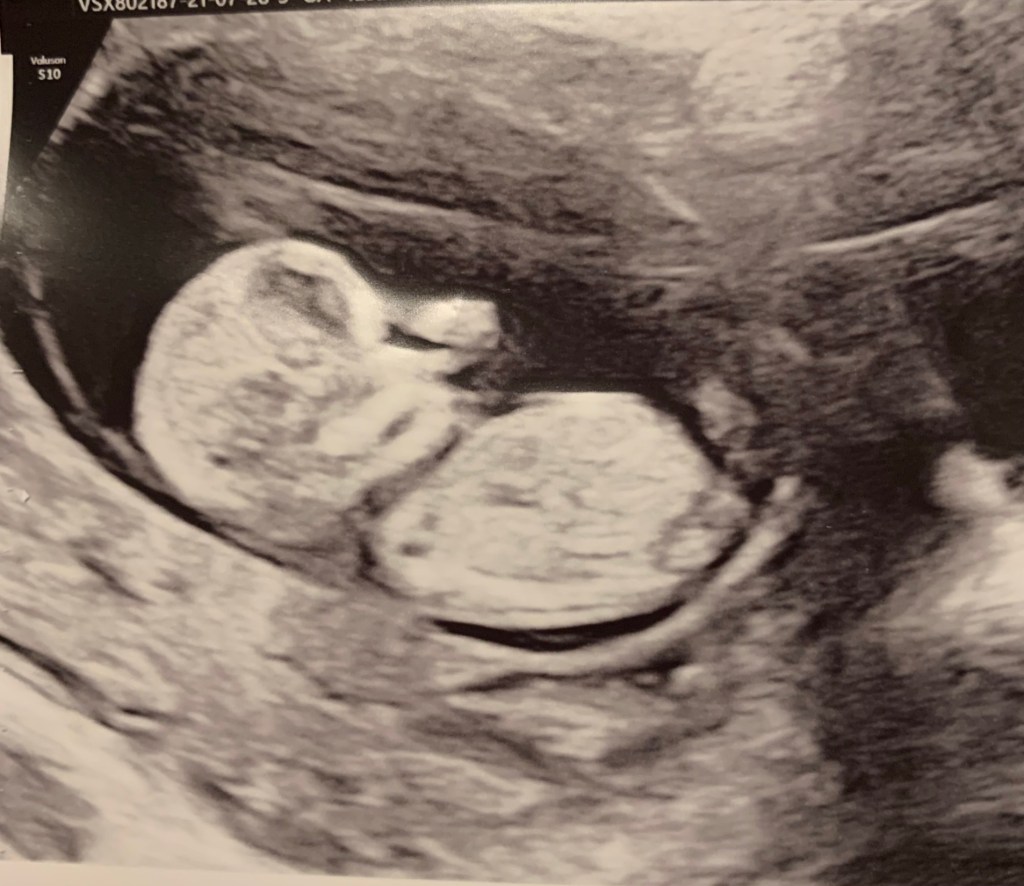

It’s really crazy how fast that little baby is growing, especially in the beginning. At 12 weeks, the baby is already 6cm big, around 20 grams and the size of a plum. Here’s my echo from around that period: